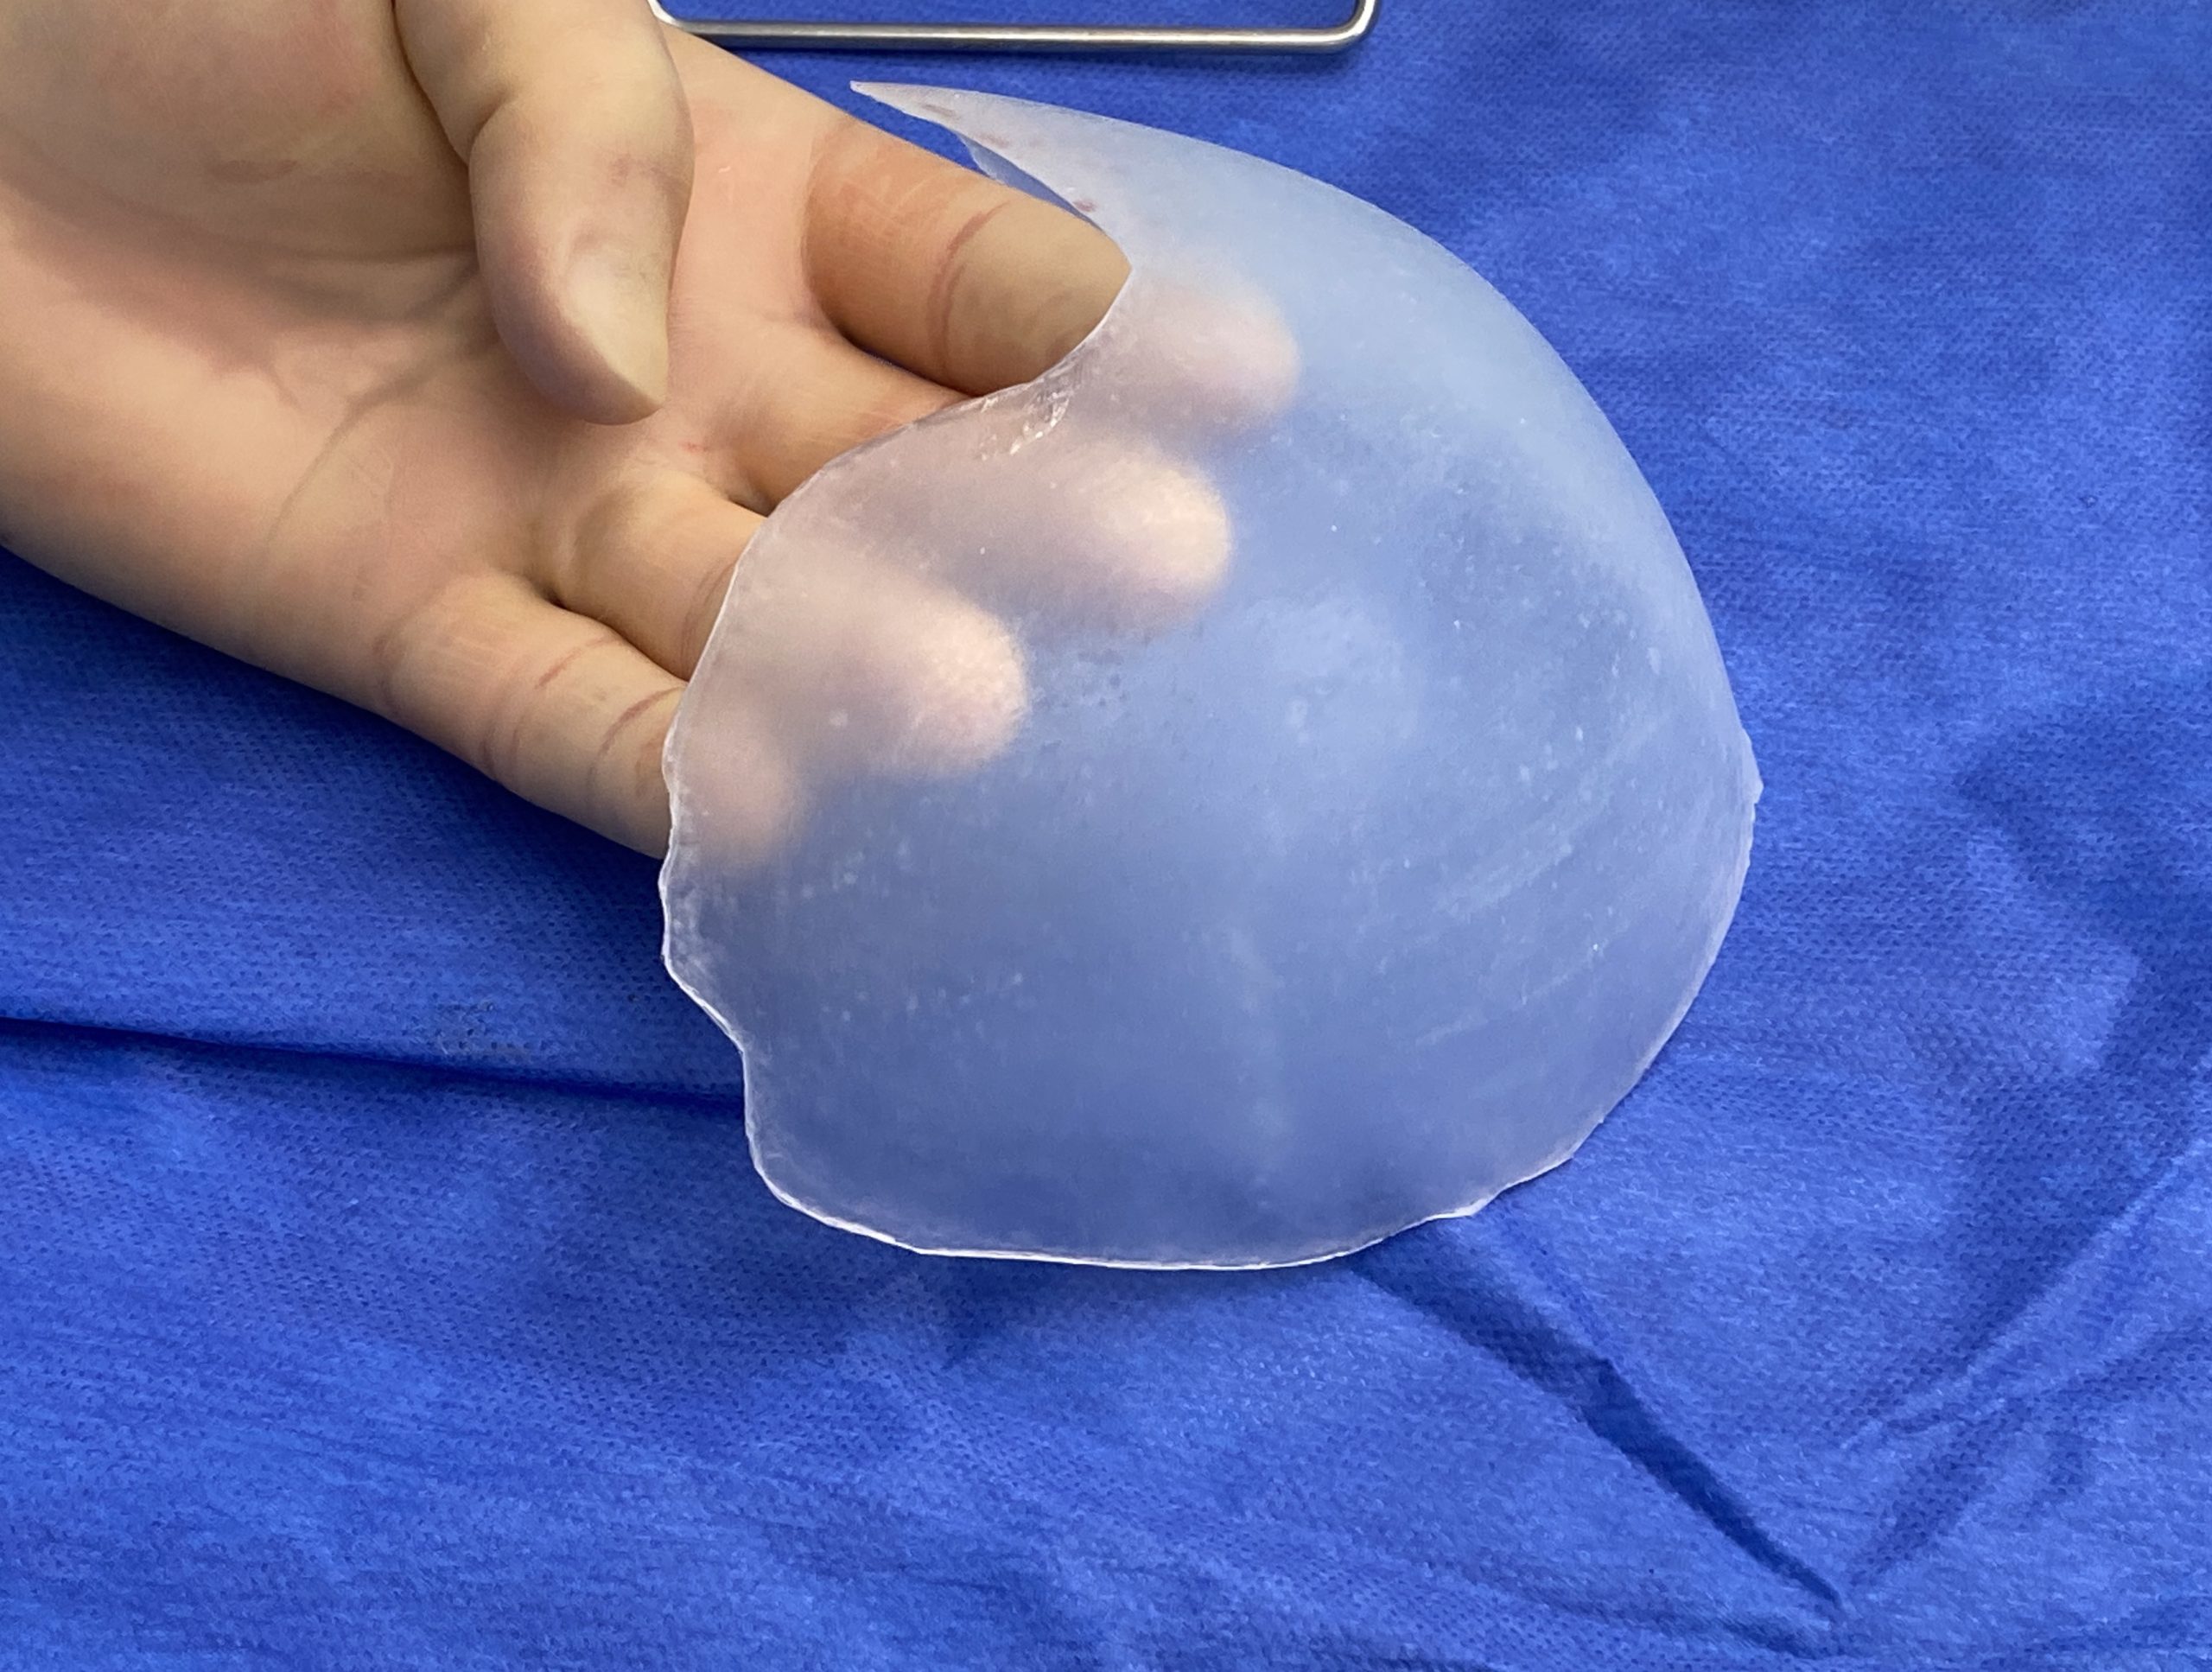

Desire for further skull augmentation after a primary skull implant.

Five years after an initial custom skull implant placement a new custom skull implant that increased the volume by 35% was placed.

Desire for further skull augmentation after a primary skull implant.

Five years after an initial custom skull implant placement a new custom skull implant that increased the volume by 35% was placed.